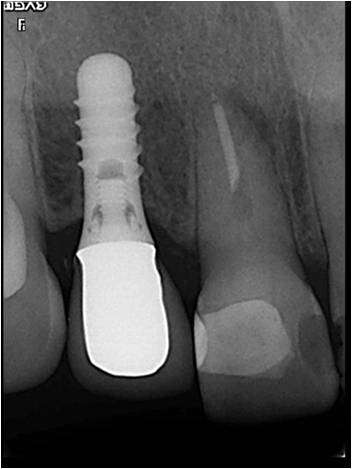

しっかり骨の中に埋められています。

この患者さんは、下の奥歯もインプラントをされました。インプラント治療後の感想を頂きました。